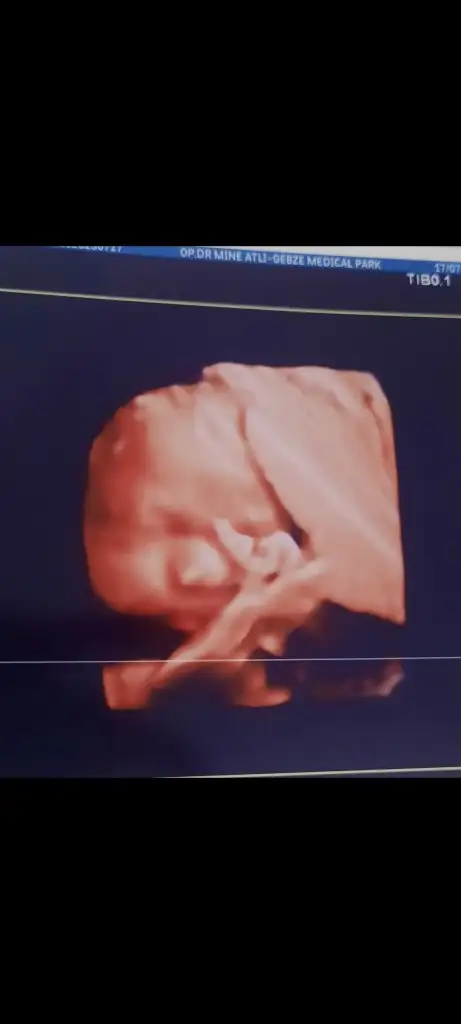

Maşallah canım çok şükürkızlar selam, 32+0 muayenesinden geldim, bebek iyi çok şükür haftasıyla uyumlu 43cm 1871 gr çıktı ( diğer ölçümlerde daha fazla gösteriyor) suyumda güzelmiş gelgelelim benim bebe dönmemiş makat geliş duruyor hala dr dedi ki senin suyun iyi inşallah döner, yeri dar olan ve suyu az olanların dönmüyormuş genelde, bi de benim tüp bebek olunca makat gelişler çok fazla oluyor tüp bebekte, bakalım henüz erken son anda bile dönen var , inşallah en hayırlısı neyse o olur, nst ye girdim güm güm kalp atışlarını dinledimondan önce sabah kalktığımdan beri o kadar hareketliydiki acayip baskıladı mesanemi , tam NST ye girerken duruldu, hemşire bebek hareketleri az aç mı geldiniz dedi bende tok gitmiştim zaten sabahtan çok hareketli olduğunu yeni durulduğunu söyledim, dr baktı sorun yok dedi, 2 hafta sonraya çağırdı